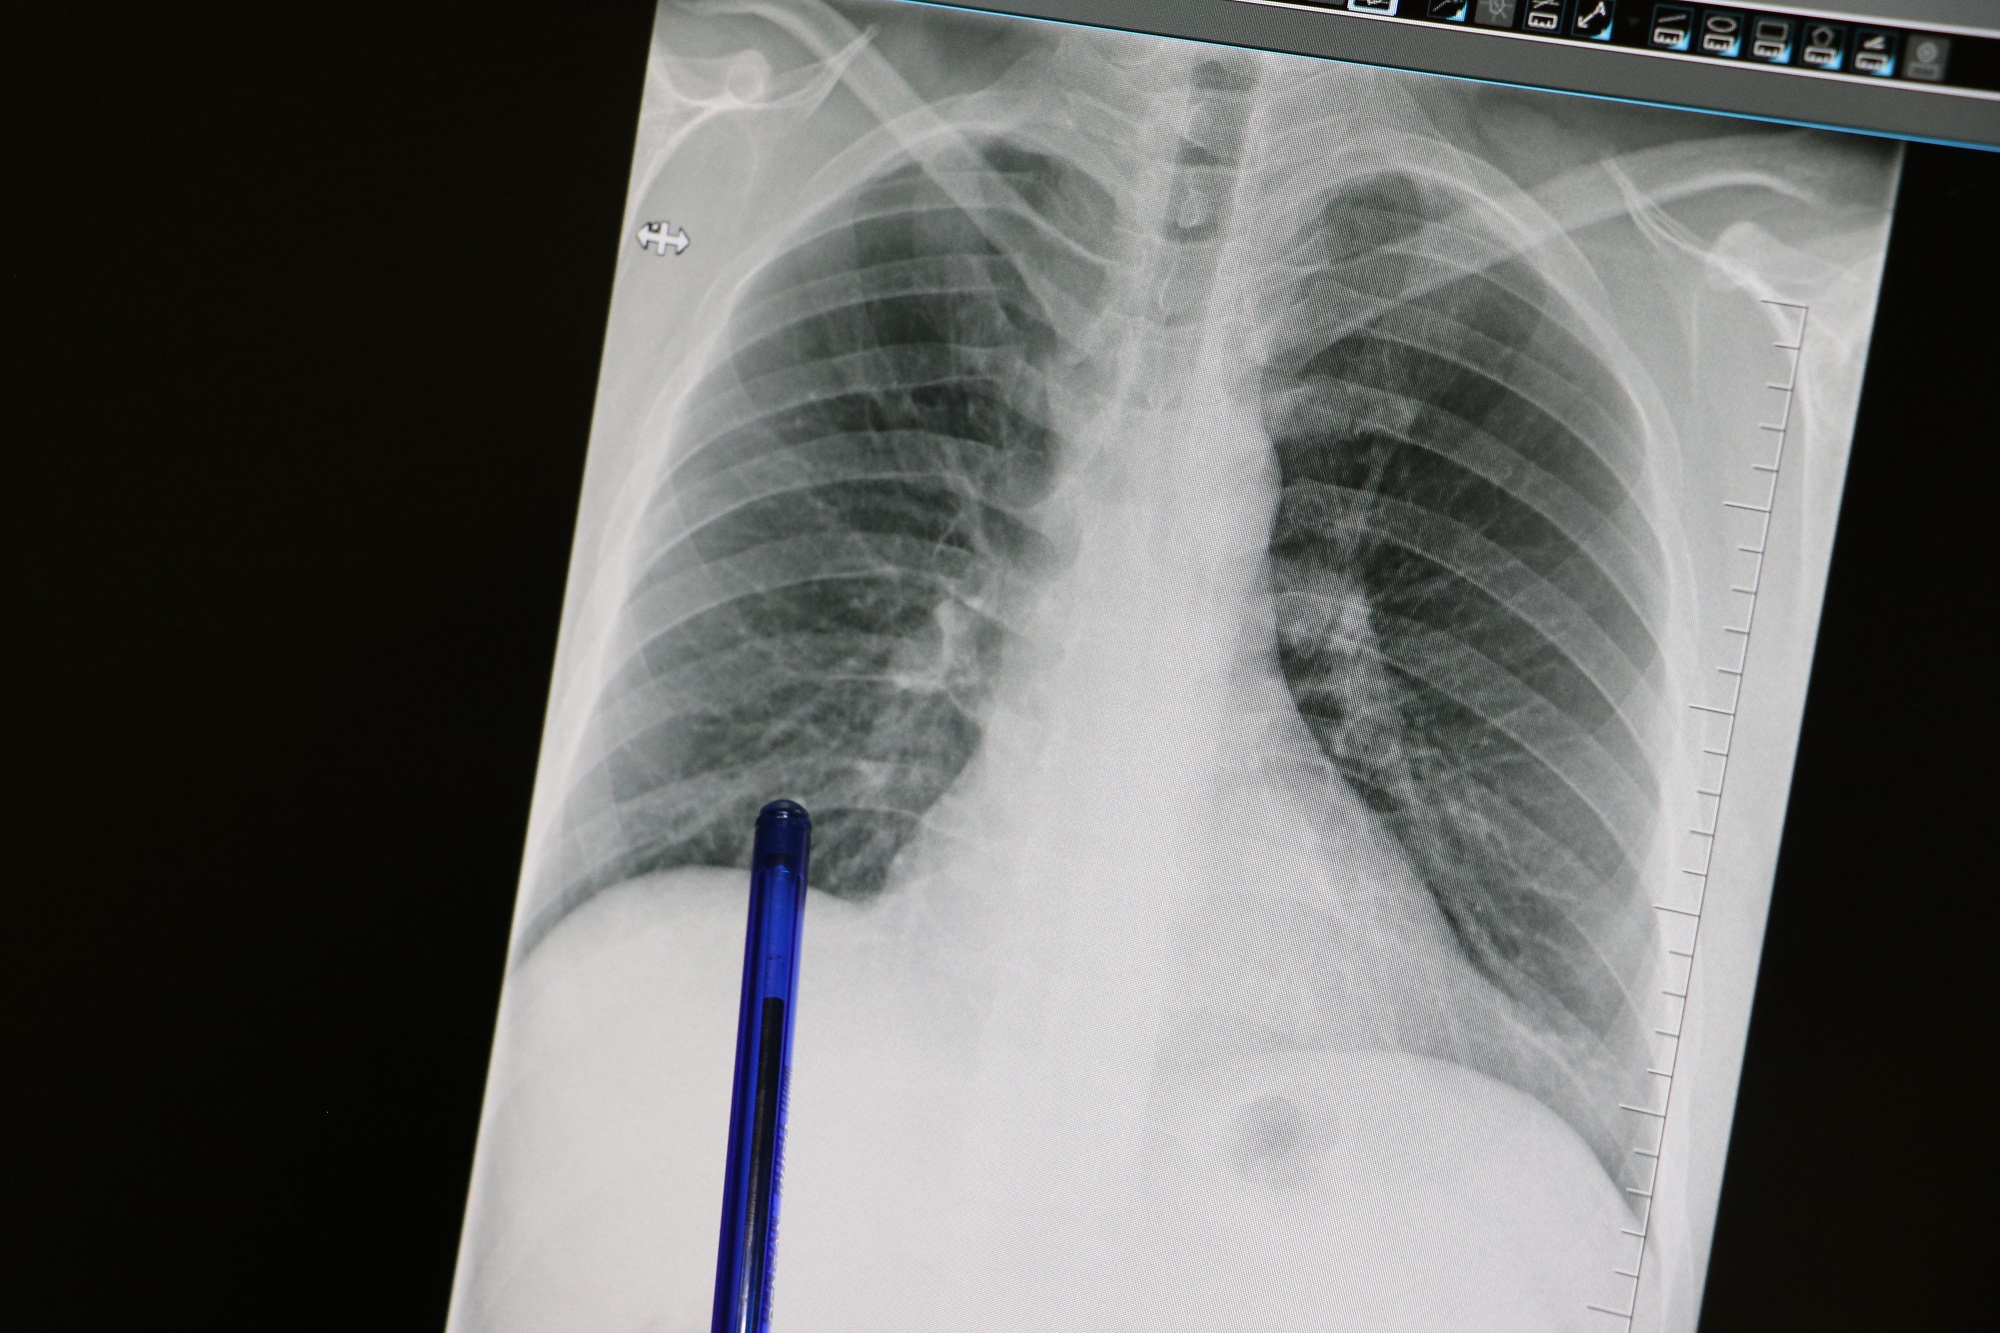

Günümüzde bilgisayarlı tomografi cihazlarının gelişmesiyle akciğerlerdeki nodülleri saptamanın kolaylaştığını ifade eden Liv Hospital Samsun'dan Uzm. Dr. Aziz Uluışık, "Kötü huylu (malign) nodüllere mümkün olduğunca erken dönemde tanı konulup ameliyat edilmesi halinde sağ kalım süresi artar. İyi (benign) nodüllerde ise gereksiz cerrahi girişimden ve buna bağlı oluşacak sorunlardan kaçınmak gerekir. Bu nedenle nodül saptandığında nasıl bir karar verileceği çok önemlidir. Günümüzde bilgisayarlı tomografi (BT) cihazlarının gelişmesi ve tomografi çekilen hasta sayısı artması sayesinde akciğerlerdeki nodülleri saptamak kolaylaştı. Akciğer tomografilerinin yaklaşık yüzde 30'unda bir veya birden fazla nodül saptama ihtimali vardır. Ancak bunların önemli mi, önemsiz mi, kötü mü yoksa iyi huylu mu olduğuna karar vermek bazı durumlarda zor olabiliyor" diye konuştu.

Uzm. Dr. Aziz Uluışık, öncelikle görülen nodülün boyutunun çok önemli olduğunun altını çizerek, "3 mm ve daha küçük nodüllerin kansere bağlı olma ihtimali yaklaşık yüzde 0,2 gibi düşük bir orandadır. 8-20 mm arasındakilerde bu ihtimal yüzde 18'e çıkarken, 20 mm'den büyük nodüllerde yüzde 64'den fazladır. Saptanan bir nodülün takibinde eski tomografiler ile karşılaştırmak önemlidir. Nodül boyutunda yüzde 25'den fazla bir artış olması kanser riskinin yüksek olduğuna işaret eder. Boyutundan sonra nodülün kenarlarının düzgün olup olmadığına bakmak gerekir. Kenarı düzensiz olan nodüllerin kanser riski 5 kat fazladır. Nodülün içinde kireçlenme bulunması, çoğunlukla iyi huylu olduğu anlamına gelir. Genellikle 2-3 yıl, bazı durumlarda ise 5 yıllık izlemde eğer nodülde bir değişiklik yoksa ileri incelemeye gerek yoktur" açıklamasında bulundu.